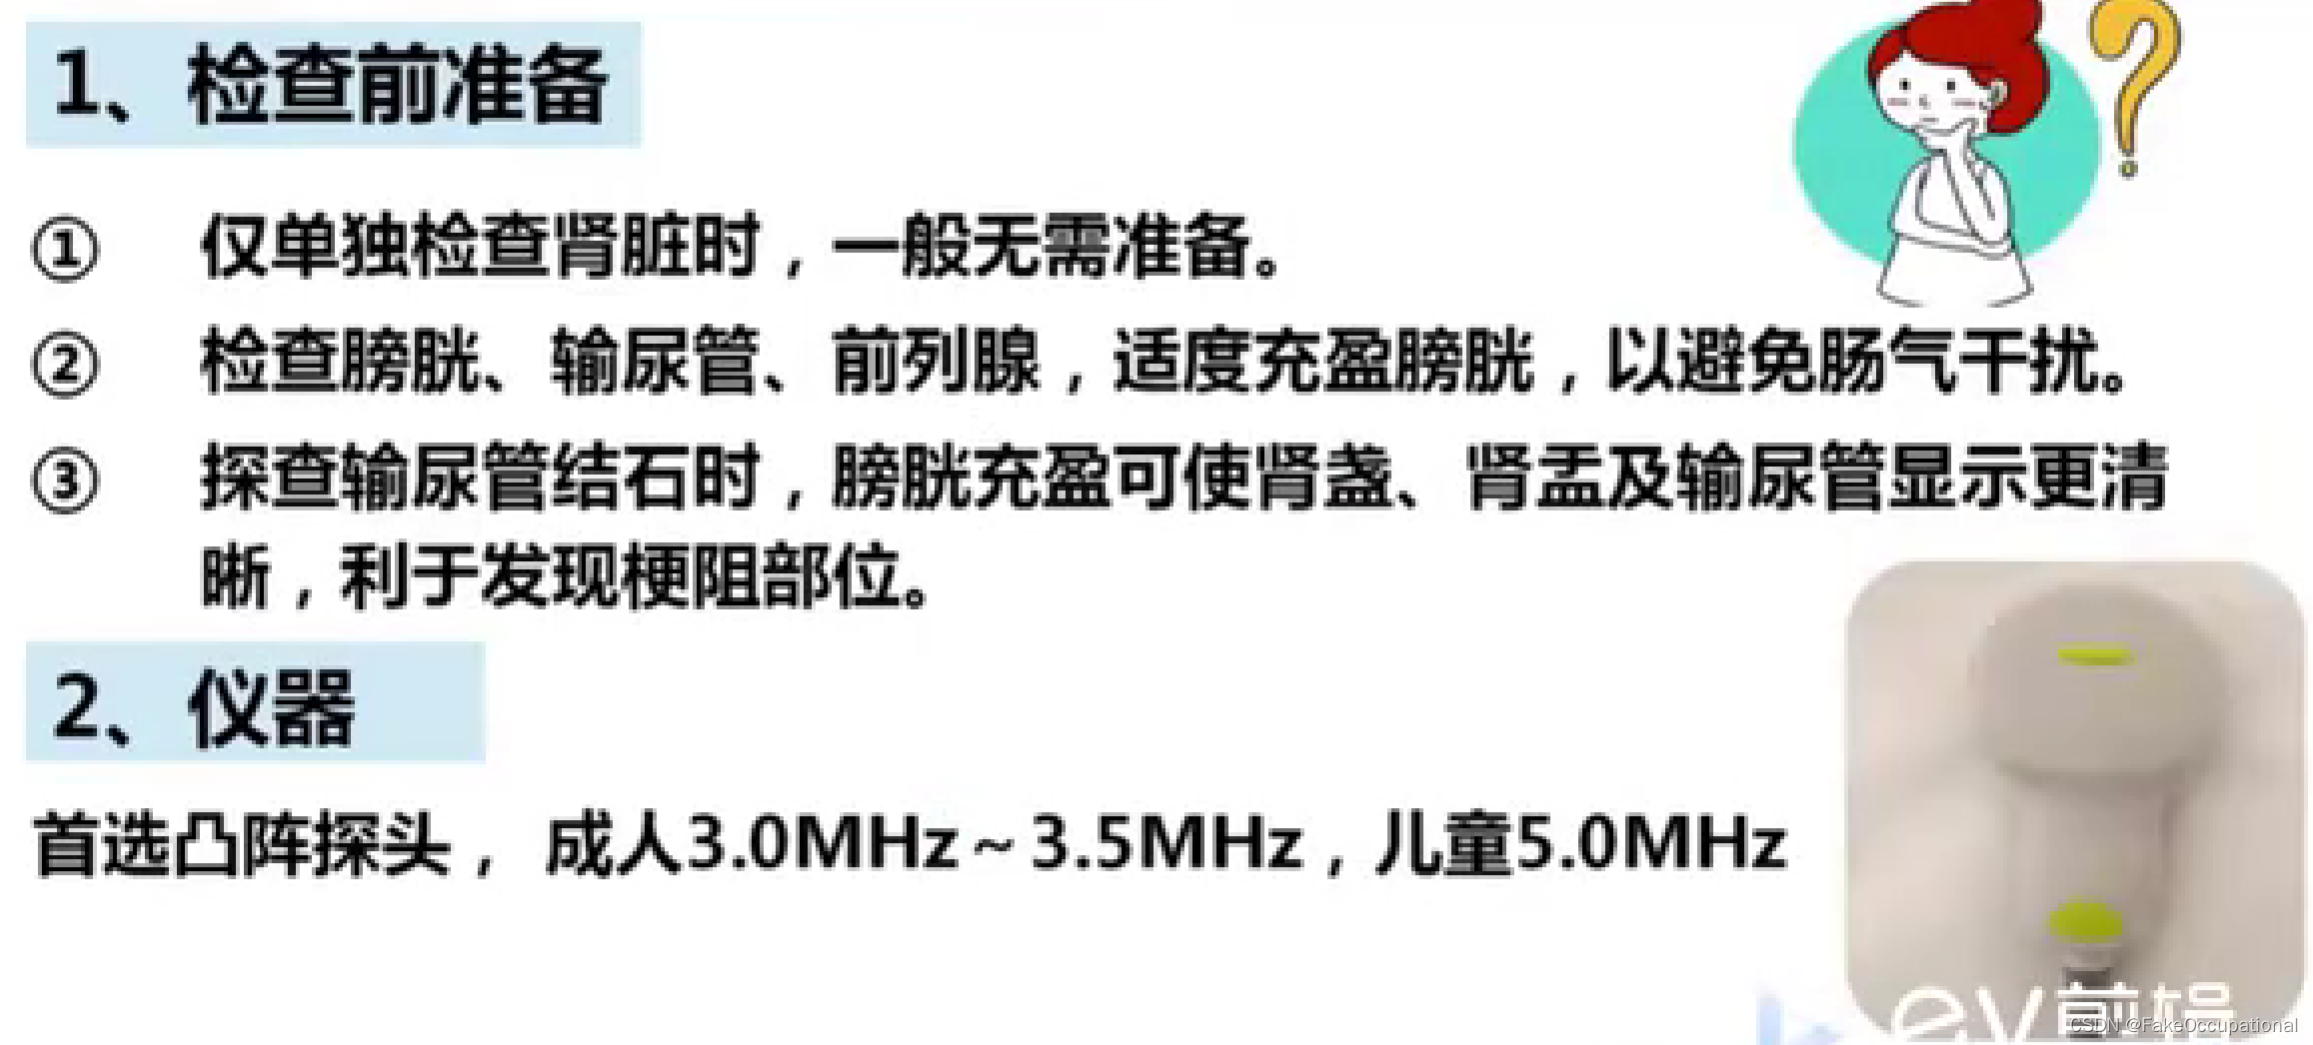

超声检查技术

探头使用

1、经腹壁探测

凸阵或扇形超声探头,成人选用频率3.5MHZ儿童选用频率5.0MHz